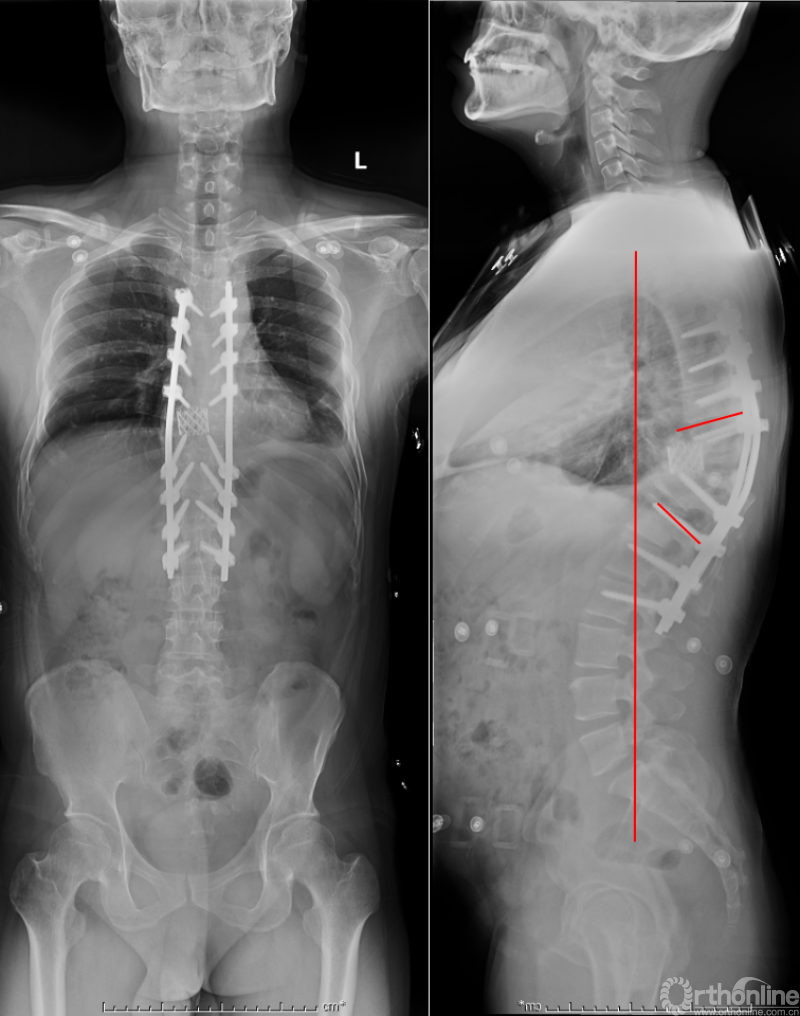

众所周知,脊椎结核后突畸形是结核病严重的后遗症之一。不仅影响患者外表仪容和心理,还可能出现晚发病灶造成截瘫。30多岁的小李就是一位脊柱结核后造成后凸畸形伴截瘫的患者,其畸形角度高达90度。针对此类患者的治疗大多就是截骨矫形,手术创伤大不说,椎体切除后造成的脊柱失稳等一系列后遗症也是令医生和患者担忧的。为解决临床上的这类问题,丁文元教授对传统的PVCR截骨技术进行了简化和改良,即后路单侧截骨部分椎体切除固定矫形术(UPVCR)入路,该技术采用后方单侧截骨,切除部分椎体、相邻椎间盘大部,保留对侧椎弓根及部分椎体,重建置入钛网支撑。随后,丁文元教授通过UPVCR技术对小李实施了手术,经过家人悉心地照顾,小李术后肌力恢复的良好,很快就出院了。三个月复查时竟是自己走路来的,临床疗效让患者及家人很是满意。

患者术前资料

患者术后资料

丁文元教授介绍说,UPVCR技术的优势在于手术操作简单,易于掌握,学习曲线短,手术时间短,出血少,神经并发症少;临床应用时极少发生断钉、断棒、不融合的现象,术中保留了良好的血运、植骨床,提供骨生长环境,保证部分骨支撑,术后极少发生矫正丢失,临床效果肯定。